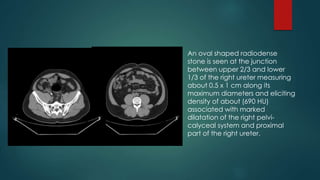

 40 Male patient complaining

of right renal colic with

hematuria

 An oval shaped radiodense

stone is seen at the junction

between upper 2/3 and lower

1/3 of the right ureter measuring

about 0.5 x 1 cm along its

maximum diameters and eliciting

density of about (690 HU)

associated with marked

dilatation of the right pelvi-

calyceal system and proximal

part of the right ureter.